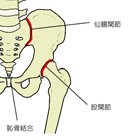

・恥骨は寛骨を構成する3つの骨のうちの一つである。3つの骨のうち前下部に位置し、閉鎖孔を前方および上方からから囲むような形になっている。 ・恥骨は、大きく恥骨体と恥骨枝の2つに分けられ、恥骨枝はさらに恥骨上枝と恥骨下枝の2つに分けられる。 ここでは、英語で画像検索をかけるとそのほとんどは恥骨結合の側部を恥骨体としているので、それに準じることにする。

【 隣 接 】 恥骨は、腸骨および坐骨とは思春期までは軟骨によって結合されるが、青年期には骨結合に置き換わり1個の寛骨となる。 また、恥骨は寛骨臼の形成にも預かっているが、寛骨臼は大腿骨と接合し股関節を形成している。 |

恥骨は、その内側にある仙骨と接合し仙腸関節を形成する。また、腸骨は寛骨臼の形成にも関わり、寛骨臼は大腿骨頭と接合し股関節を形成している。